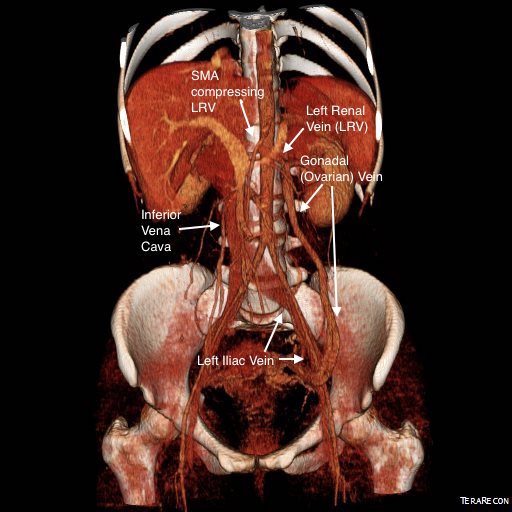

CT Venography showed the gonadal vein to be an important outflow vessel to the left renal vein with dilated proximal segment and reflux into pelvic varices.

A left gonadal vein to iliac vein transposition was planned via a left lower quadrant retroperitoneal exposure. On the table, a venogram was performed with selective access of the left renal vein.

The injection from the LRV showed severe compression of the LRV with a channel only slightly larger than the sheath and avid reflux into the gonadal vein. Selective access into the gonadal vein and venography from a confluence in the pelvis showed that flow was one way from the LRV into the gonadal vein and this filled a large region of pelvic varices.